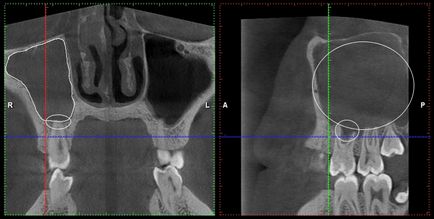

Cyst felső állkapocs (konzervatív kezelés)

Ciszta maxillaris fog, fogeredetű arcüreggyulladás

Hely bölcsességfog gyökerei az arcüreg